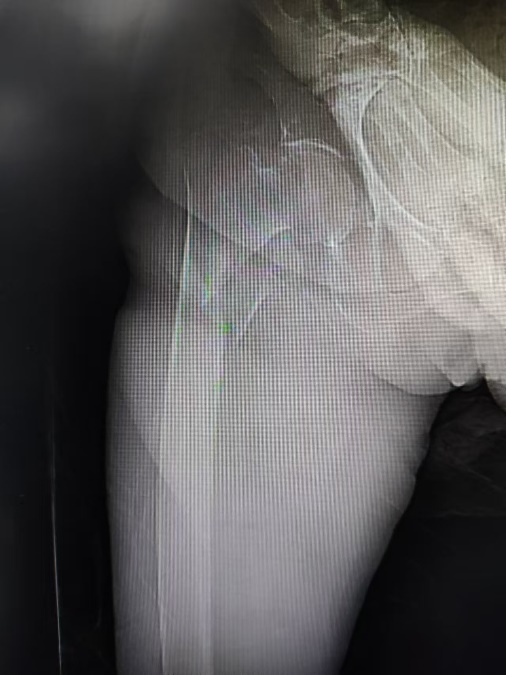

92岁老人在家中不慎摔倒,导致髋部骨折,疼痛难忍,无法站立。由于她高龄,长期患有糖尿病、慢性肾病、高血压、心脏病等多种合并症,且未进行规律治疗,血糖一度高达25mmol/L,并已出现嗜睡,神智淡漠等情况,家属陪同老人在多家医院辗转就诊,均因病情复杂评估无手术条件,但家属并未放弃,慕名来到了我院骨病与创伤科就诊。接诊患者的是我科老年骨科专病专家薛建利副教授,面对如此高龄且病情复杂的患者,薛教授秉承“以人为本,生命至上”的治疗理念,仔细评估患者病情,并与家属充分沟通后,决定救治该患者。

考虑患者手术的紧迫性,一旦错过手术时间窗,很难再有手术治疗机会,在多学科协作治疗下,医疗团队在患者入院第三天便为其进行了急诊手术。手术过程中,麻醉科吕建瑞主任主导,赵静医师全程保驾护航,在程斌主任指导下,薛建利副教授带领叶劲涛医师手术团队凭借其过硬的手术技艺,成功为患者实施了股骨粗隆间骨折髓内钉内固定术,骨折部位精准固定,手术损伤小,切口仅约6cm,术中出血仅约30毫升,整个手术过程流畅而高效,仅用时1小时。